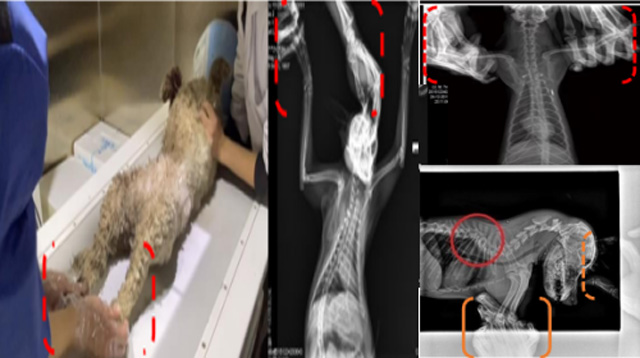

现在宠物医疗设备得到高速发展,现在有越来越多的宠物诊疗机构配置X射线装置如宠物DR。宠物骨折或者有其他疾病不能通过直观看出来的。宠物诊所医生都会使用宠物DR来做辅助检查。但是有时候宠物医生没有加强防护,就在宠物DR室给宠物拍X片做检查。这样也是会受到X射线的辐射。因为X射线上岗是属于职业病危害岗位。长期的辐射会对人体造成一定的危害。宠物医生也需要接受X射线照射的上岗前都必须进行放射工作人员的职业健康体检。体检不合格的话是不能担任放射工作的。未经上岗前职业健康体检的劳动者从事接触职业病危害作业的行为,已经违反了《中华人民共和国职业病防治法》第三十五条规定,依据《中华人民共和国职业病防治法》第七十五条规定,需要进行整改罚款。开展宠物放射诊疗活动,在日常工作中,对本机构的X射线危害的职业病防治,需要知道并做到以下内容: